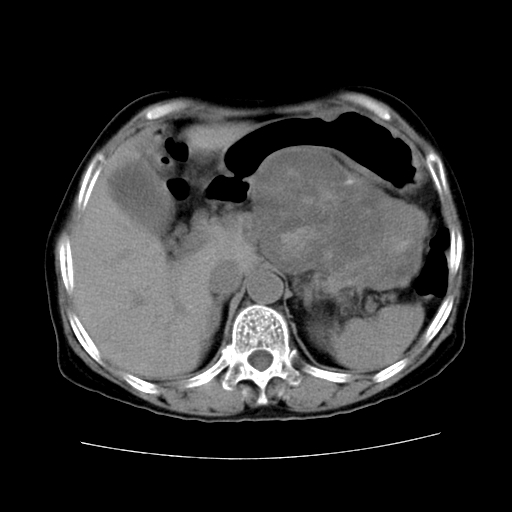

女性,72岁。

主诉中上腹部疼痛不适1年余。

胰腺尾部不规则巨大略低密度肿块,界限清楚,内密度不均,增强动脉期不均匀强化,门脉期明显退减并低于胰腺密度,肿瘤包埋于脾血管。多考虑;来源于胰腺尾部的“胰腺癌”。

该例有几个特点需注意:

1.肿瘤大而边界清

2.内部有钙化

3.强化时间较长

4.这么大的肿瘤对周围的血管无侵犯

以上几条均与胰腺癌不符

故考虑:胰岛细胞癌

1、这个病例确实有点难。影像主要显示胰腺体尾部占位,我们当初也是诊断胰体尾部囊腺癌可能性大,而且读片会上也很多人这么诊断的。

2、手术所见:打开腹腔发现胃与胰腺体尾部可见肿块,大小约10×8×11cm,质硬,不可推动,周围血供丰富。术中诊断:胃肿瘤侵及胰腺体尾部。

3、病理号:091860 2009年4月2日

1)、胃小弯侧胃肠间质瘤(考虑恶性),瘤体大小13.5×7×6.5cm,上下切缘阴性。

2)、胃小弯1只、幽门下2只淋巴结慢性炎。免疫组化:cd117(+)、cd34(+)、sma(+)、desmin(-)、s-100(-)、ki-67<10%(+).

4、这个肿瘤太大了,而且密度不均性强化,从这点我们应该不能单纯诊断胰腺癌,而应想到目前流行的胃肠道间质瘤。这个肿瘤主要发生于胃壁浆膜层,所以显示与胃壁关系不是很紧密,故而大多认为是胰腺癌。